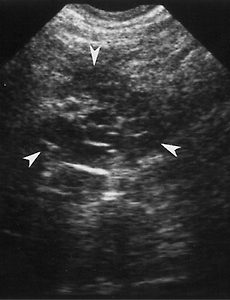

Microcystic Adenomas of the Pancreas Microcystic adenoma in a 51-year-old woman. (a) Transverse US image shows a mass in the head of the pancreas (arrowheads) containing multiple small cysts. (b) US image obtained with the patient in the decubitus position shows a dilated common bile duct (D) and gallbladder (G) due to obstruction by the pancreatic mass (arrowheads). 2009. 9. 7. 이전 1 다음